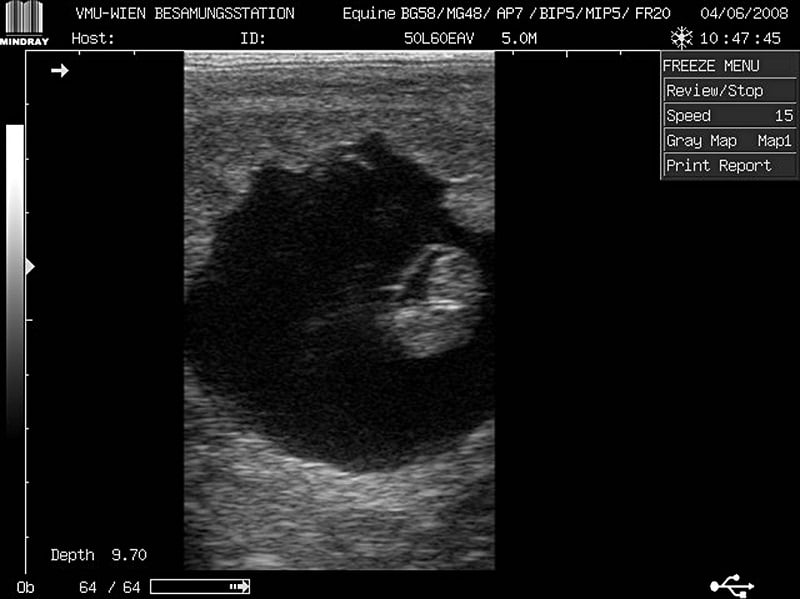

Trächtigkeitsdiagnostik aus medizinischer Sicht